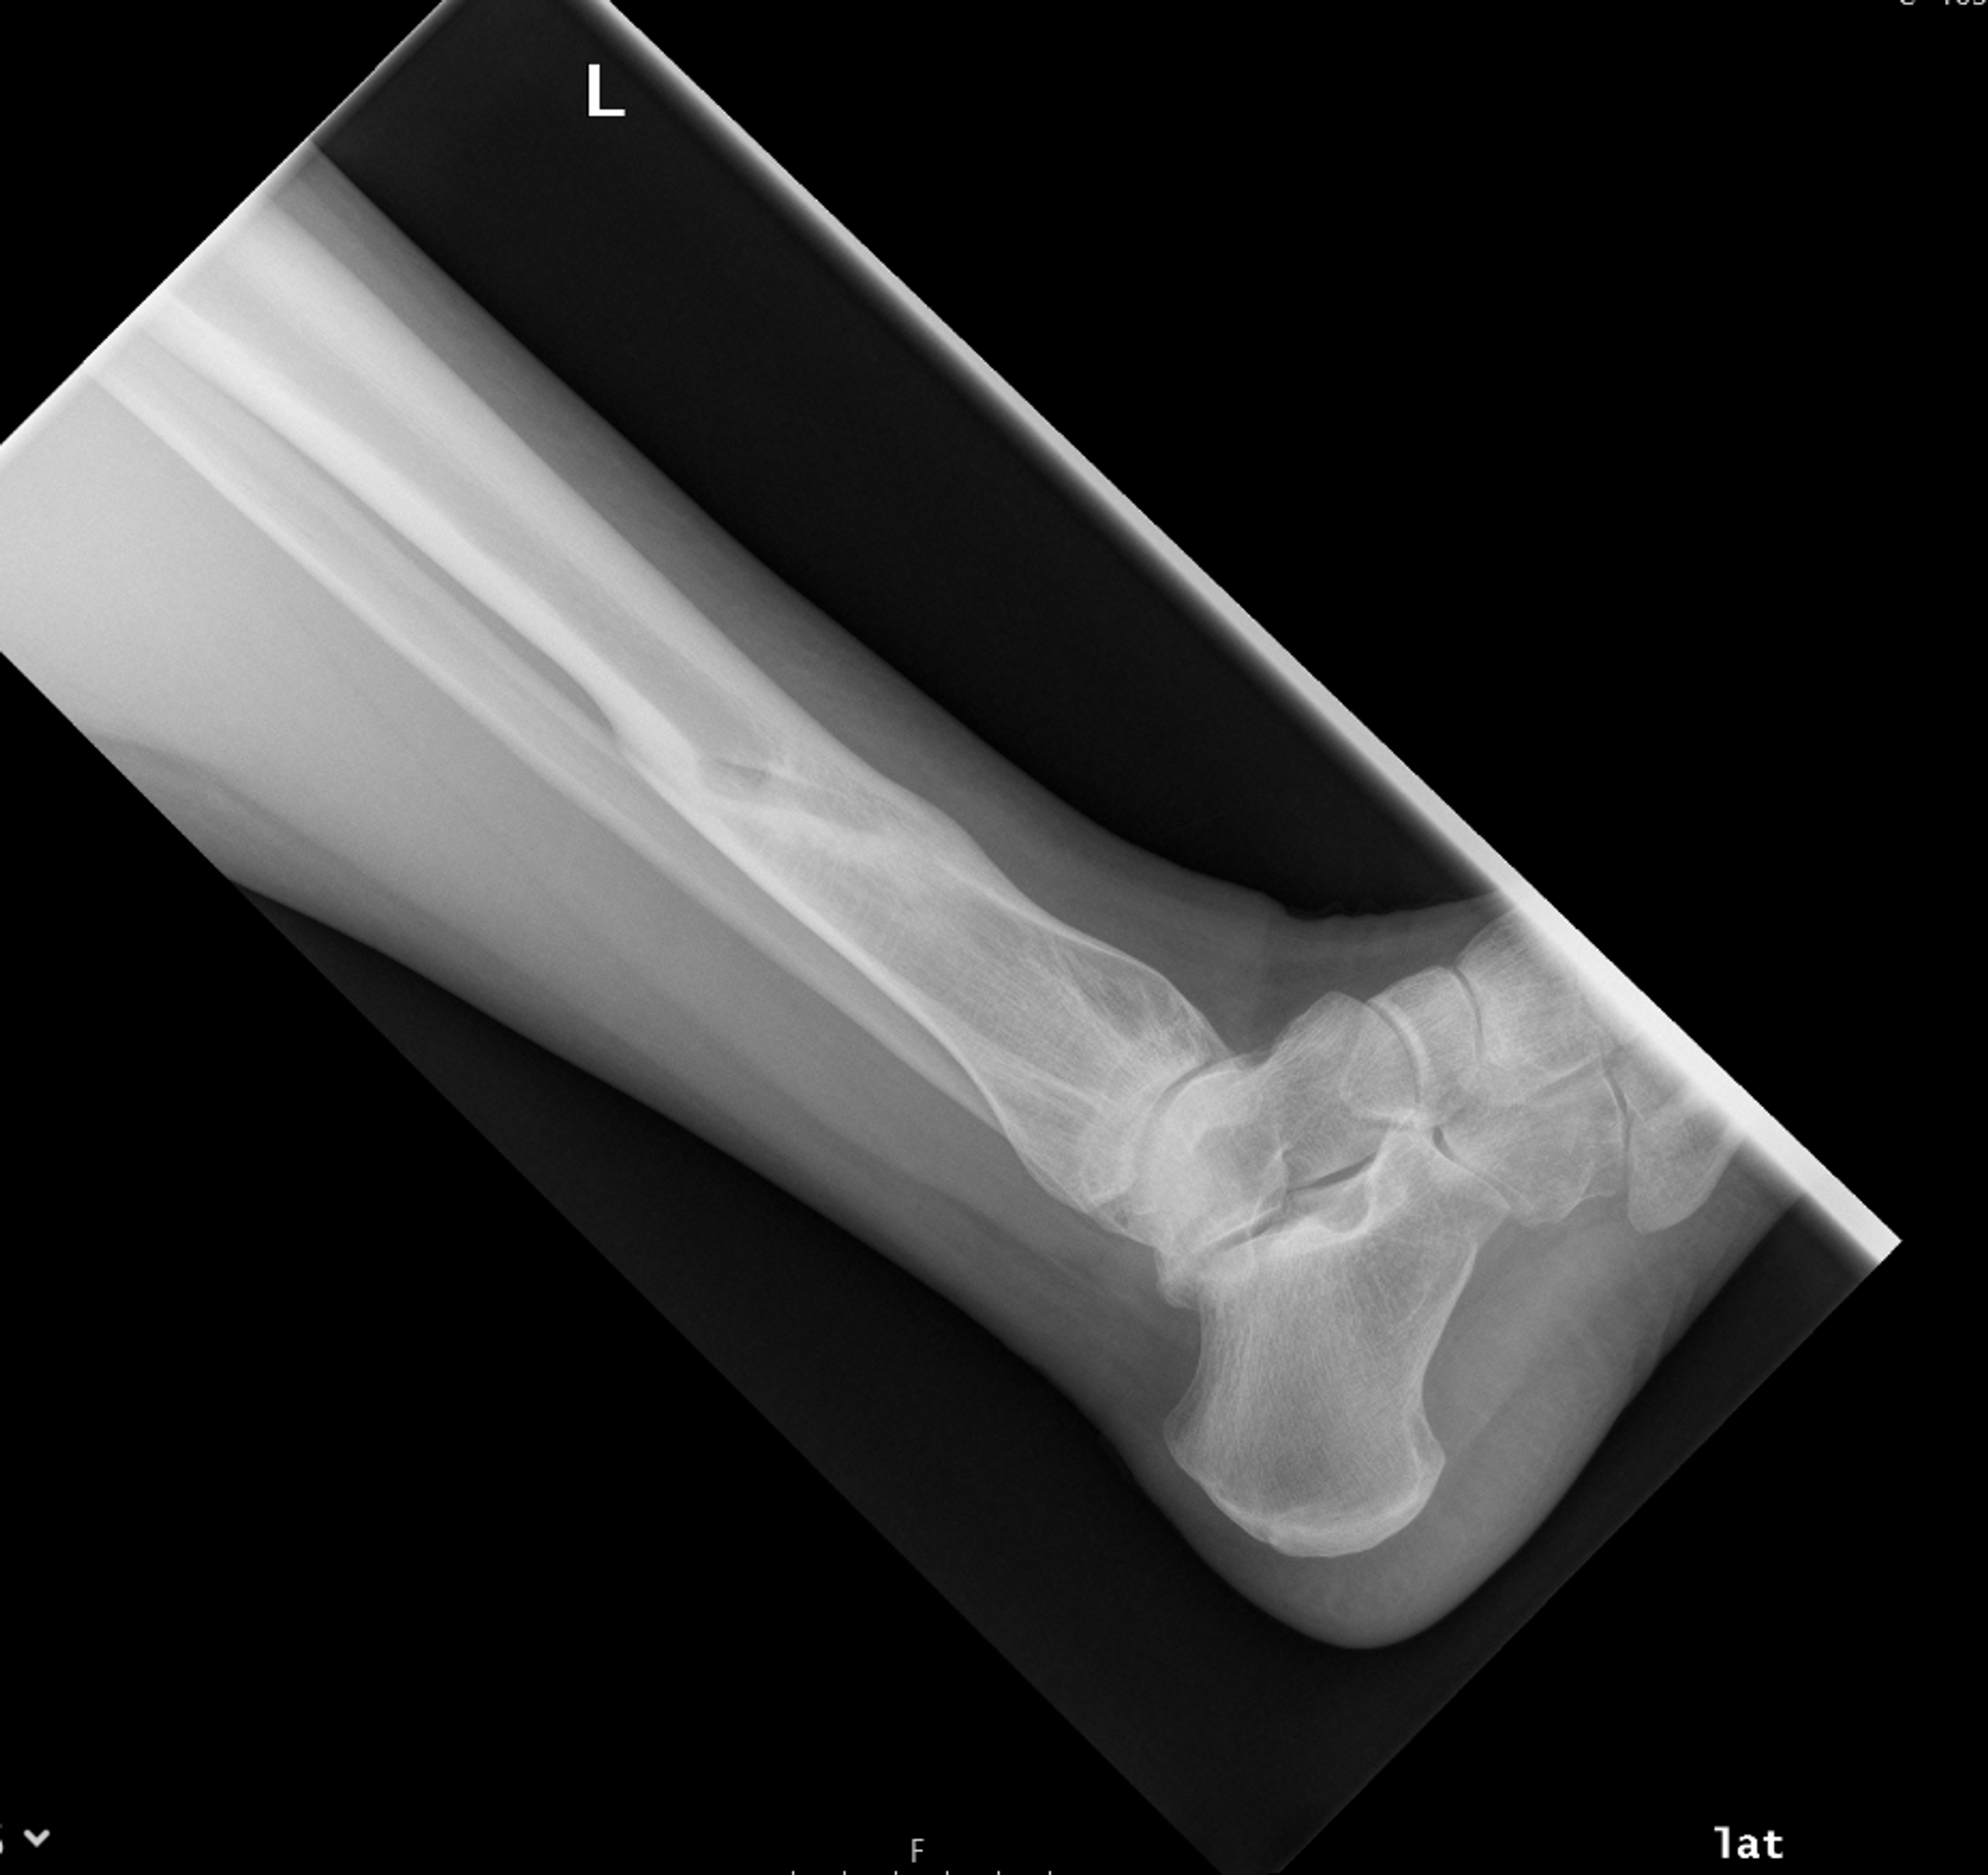

Non Union Radiology . Web this case shows abnormal fracture healing in the tibia and fibula with pseudoarticulation formed in the tibial aspect. • obliques may be helpful for radiographic diagnosis of nonunion • ct can be helpful but metal artifact can make it. Identify the etiology and epidemiology of nonunion of bone medical conditions and emergencies.

• obliques may be helpful for radiographic diagnosis of nonunion • ct can be helpful but metal artifact can make it. Web this case shows abnormal fracture healing in the tibia and fibula with pseudoarticulation formed in the tibial aspect. Identify the etiology and epidemiology of nonunion of bone medical conditions and emergencies.